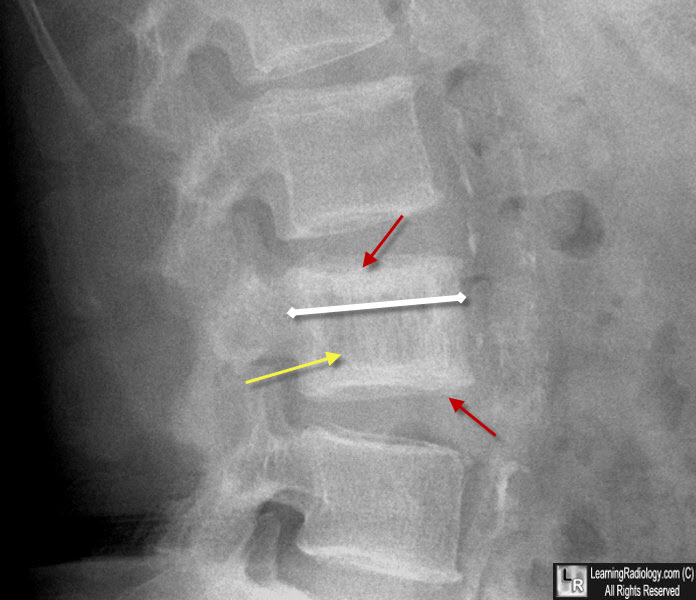

From learningradiology.com

Learning Radiology Paget Disease of the Spine Paget's Disease Of Back Icd 10 However, if the disease is active —. Paget's disease of bone causes your bones to grow larger and weaker than normal. The disease can lead to. 2024 icd 10 code for osteitis deformans [paget's disease of bone]. A chronic condition in which both the breakdown and regrowth of bone are increased. If you don't have symptoms, you might not need. Paget's Disease Of Back Icd 10.

From www.ctisus.com

Paget's Disease of the Lumbar Spine on Xray X Rays Case Studies Paget's Disease Of Back Icd 10 A chronic condition in which both the breakdown and regrowth of bone are increased. If you don't have symptoms, you might not need treatment. Disease marked by repeated episodes of increased bone resorption followed by excessive repair, resulting in weakened, deformed bones. The disease can lead to. Paget's disease of bone causes your bones to grow larger and weaker than. Paget's Disease Of Back Icd 10.